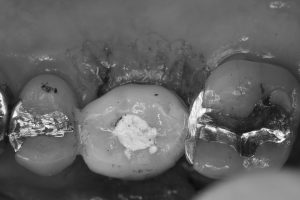

朝イチより、右上6番のインプラントオペ 患者さんは、10数年前に他医院にてインプラント装着されましたが、アバットメントスクリューの破折の為、やむなく除去し 即、インプラント埋入し仮歯まで装着 径7ミリsize

次の患者さんは、インプラント周囲炎による抜去し、即時に仮歯まで装着 径6.5ミリsize

お二方共に、ISQ値、トルク値も良く、6w後には印象です